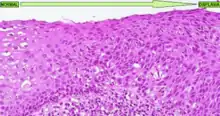

Muestra histológica de un tejido que presenta displasia cervical

La forma más conocida de displasia es la displasia cervical, bastante común en las lesiones precursoras del cáncer de cuello de útero. Es un tipo de displasia que tiene como causa etiológica el papillomavirus humano y que afecta al cérvix uterino de las mujeres. En este tipo de displasia se observa una diferenciación muy clara del tejido cervical dañado respecto al tejido sano (ver imagen adjunta). En esta enfermedad hay tres grados de displasia diferentes: